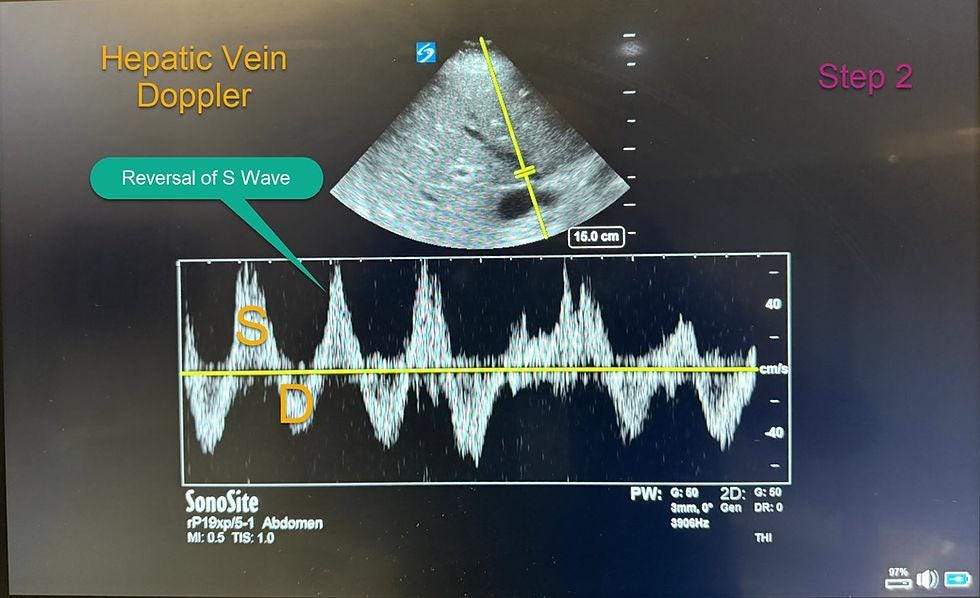

Step 2: Hepatic Vein Doppler

How to Obtain the View

Subxiphoid approach:

Probe below xiphoid, marker at 12 o’clock

Tilt right to visualize hepatic vein entering IVC

Coronal approach (preferred):

Place probe along line from xiphoid to midaxillary line

Marker toward right axilla

Slide cephalad and tilt downward

Doppler technique:

Use color Doppler to identify vein

Place sample volume 1–2 cm from HV-IVC junction

Avoid junctions

Interpretation

S > D → normal

S < D → mild congestion

S reversal → severe congestion

Pitfalls

Atrial fibrillation (absent A wave)

Tricuspid regurgitation (persistent S reversal)

Cirrhosis (blunted waveform)

Lack of ECG correlation